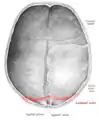

![]() Lambdoid suture (labeled at bottom right) | |

The lambdoid suture (or lambdoidal suture) is a dense, fibrous connective tissue joint on the posterior aspect of the skull that connects the parietal bones with the occipital bone. It is continuous with the occipitomastoid suture.

The lambdoid suture is between the paired parietal bones and the occipital bone of the skull. It runs from the asterion on each side.

The lambdoid suture is named due to its uppercase lambda-like shape.

Lambdoid suture seen from above.